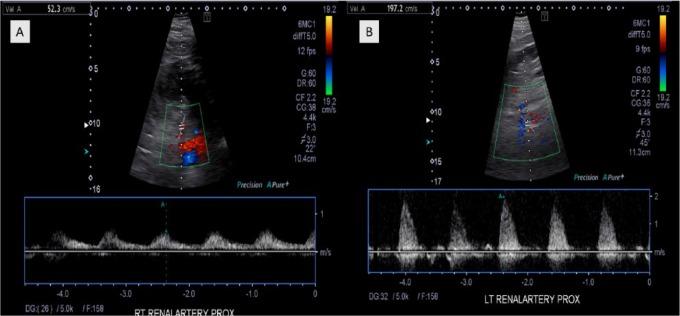

Recurrent Pleural Effusion as a Result of Bilateral Renal Artery Stenosis. Does Renal Revascularization Help?

Renal artery stenosis (RAS) is the leading cause of secondary hypertension. Renal artery stenosis can result in various cardiopulmonary complications mostly through activation of neurohormonal pathways that result in fluid overload and systemic hypertension. We herein describe a 72-year-old man with recurrent rapidly accumulating transudative pleural effusion in a patient with severe bilateral RAS. Patient pleural effusion resolved following stent placement with revascularization of the left renal artery despite absence of improvement of renal function. Patient renal function continued to decline and ultimately treated with fixed hemodialysis.